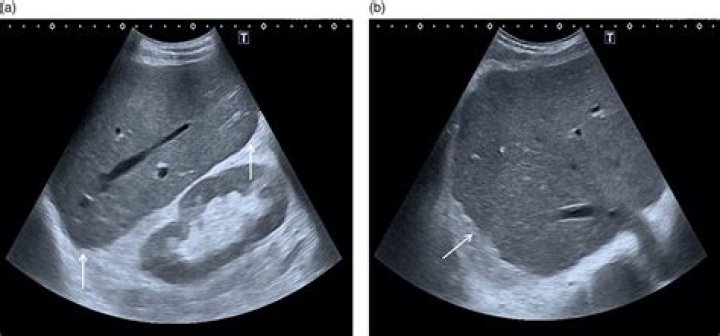

What is echogenic liver?

An echogenic liver is defined as increased echogenicity of the liver parenchyma compared with the renal cortex. The prevalence of echogenic liver is approximately 13% to 20%. In most clinical settings, increased liver echogenicity is simply attributed to hepatic steatosis.

Is echogenic liver bad?

It’s also found through imaging — such as ultrasound, CT scan or MRI — which can reveal increased echogenicity. That usually means the liver is more dense than normal toward sound waves. While imaging doesn’t directly measure fat, increased echogenicity is almost always related to excess fat in the liver.